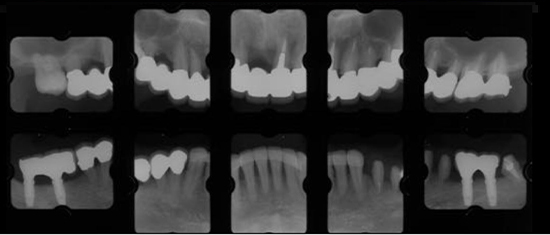

治療中01

治療中02

治療中03